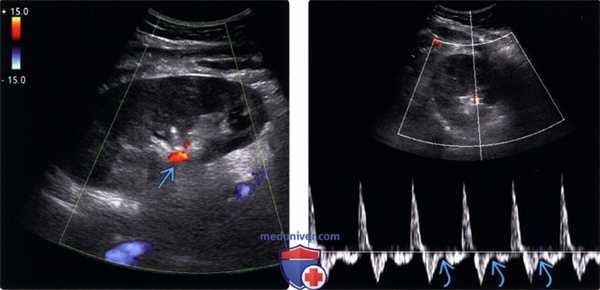

(Левый) На продольном УЗ срезе с цветовой допплерографией почечного трансплантата в первые послеоперационные сутки визуализируется отсутствие васкуляризации паренхимы. Единственная область с видимым кровотоком — артериальный сигнал в воротах почки.

(Правый) При спектральной допплерографии у этого же пациента визуализируется пандиастолическая регургитация в основной почечной артерии, развившаяся вследствие острого тромбоза почечной вены. Кровоток по почечной вене у этого пациента восстановить не удалось, в связи с чем на третьи сутки потребовалась трансплантатэктомия.